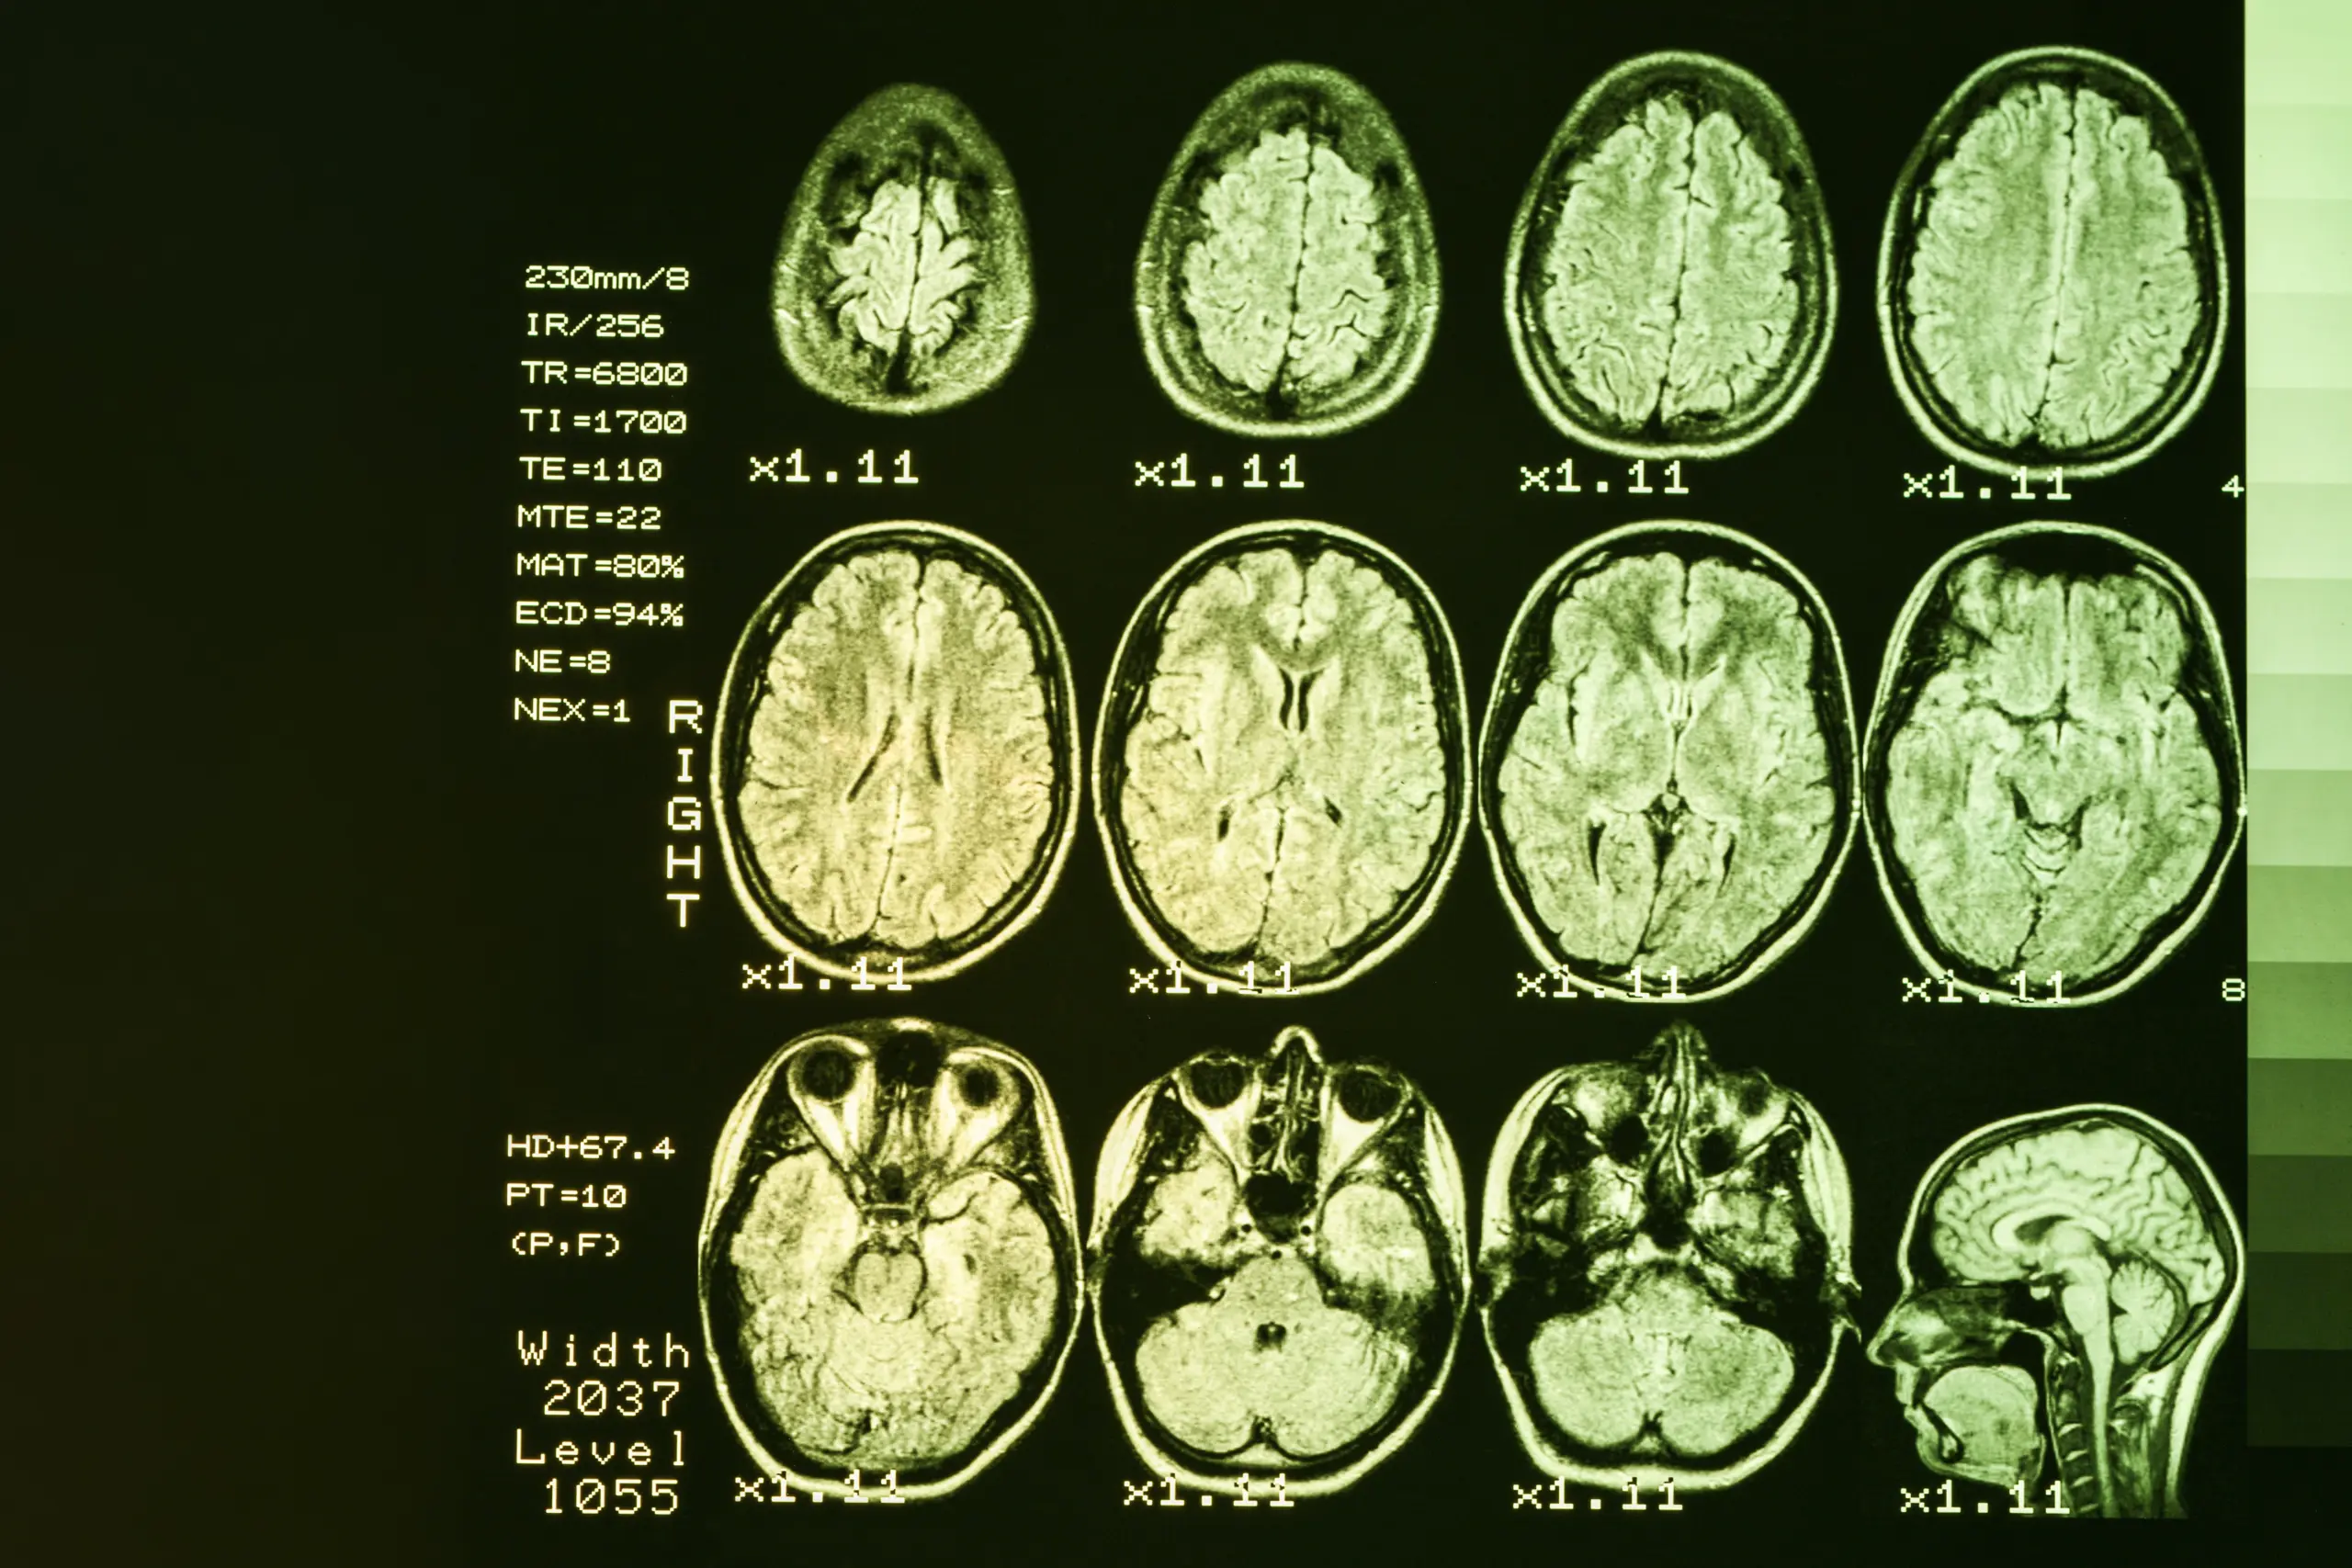

The current diagnosis of Huntington’s disease includes a physical exam, a review of individual and family medical history, and neurological and psychiatric evaluation. Physicians may order brain imaging scans for structural and functional details. Predictive genetic testing can also help individuals evaluate their risk of developing the disease.